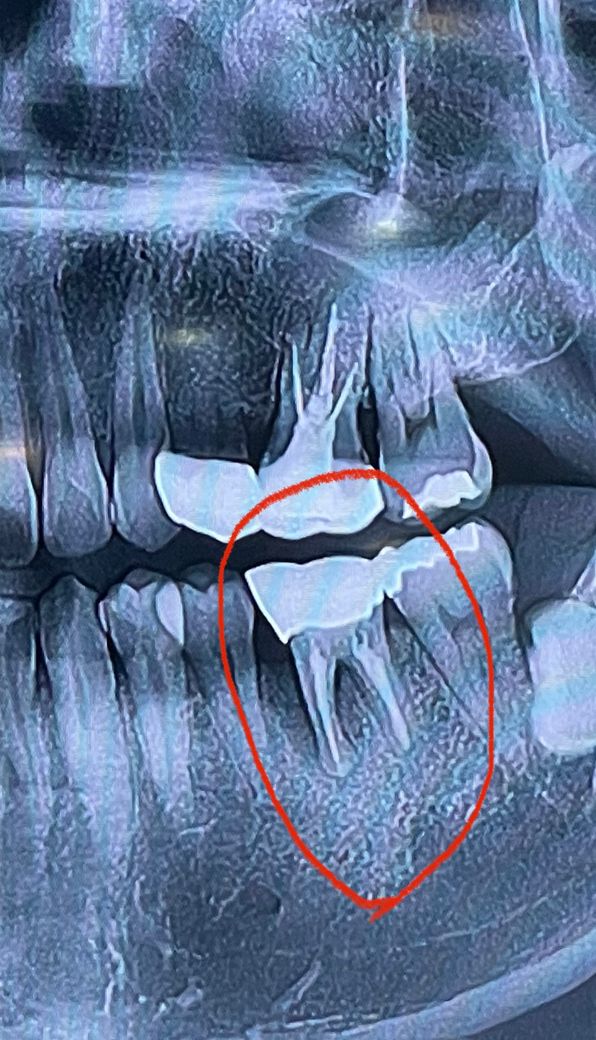

잇몸이 많이 내려 앉고 고름까지 나고 있습니다

• 1번 째 사진

치과대학병원 가신다면 구강외과 찾아가서 혹시 치아뿌리 한가닥만 절단하는 수술 가능한지 상담 받아 보기를 권합니다. 뿌리 2가닥 중 1가닥에 염증이 심하니 심한 뿌리만 절단하는 수술이 가능할 지도 모릅니다.

치주과에 내원하셔서 검사를 받아보시면 되고 사진 상으로는 살리기는 힘들어 보입니다..